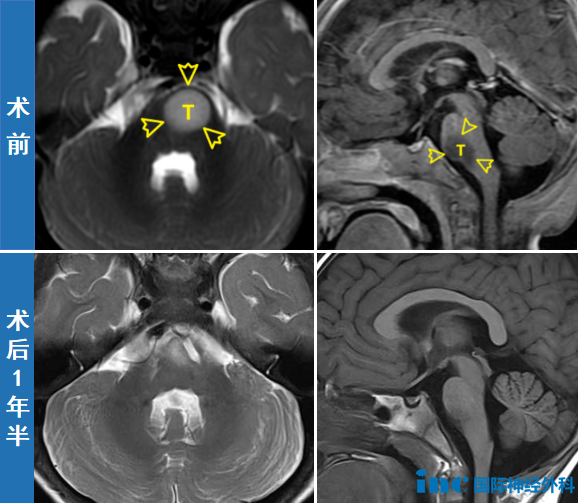

头颅磁共振成像(MRI)发现:第四脑室下方-枕大孔区-上段颈椎椎...